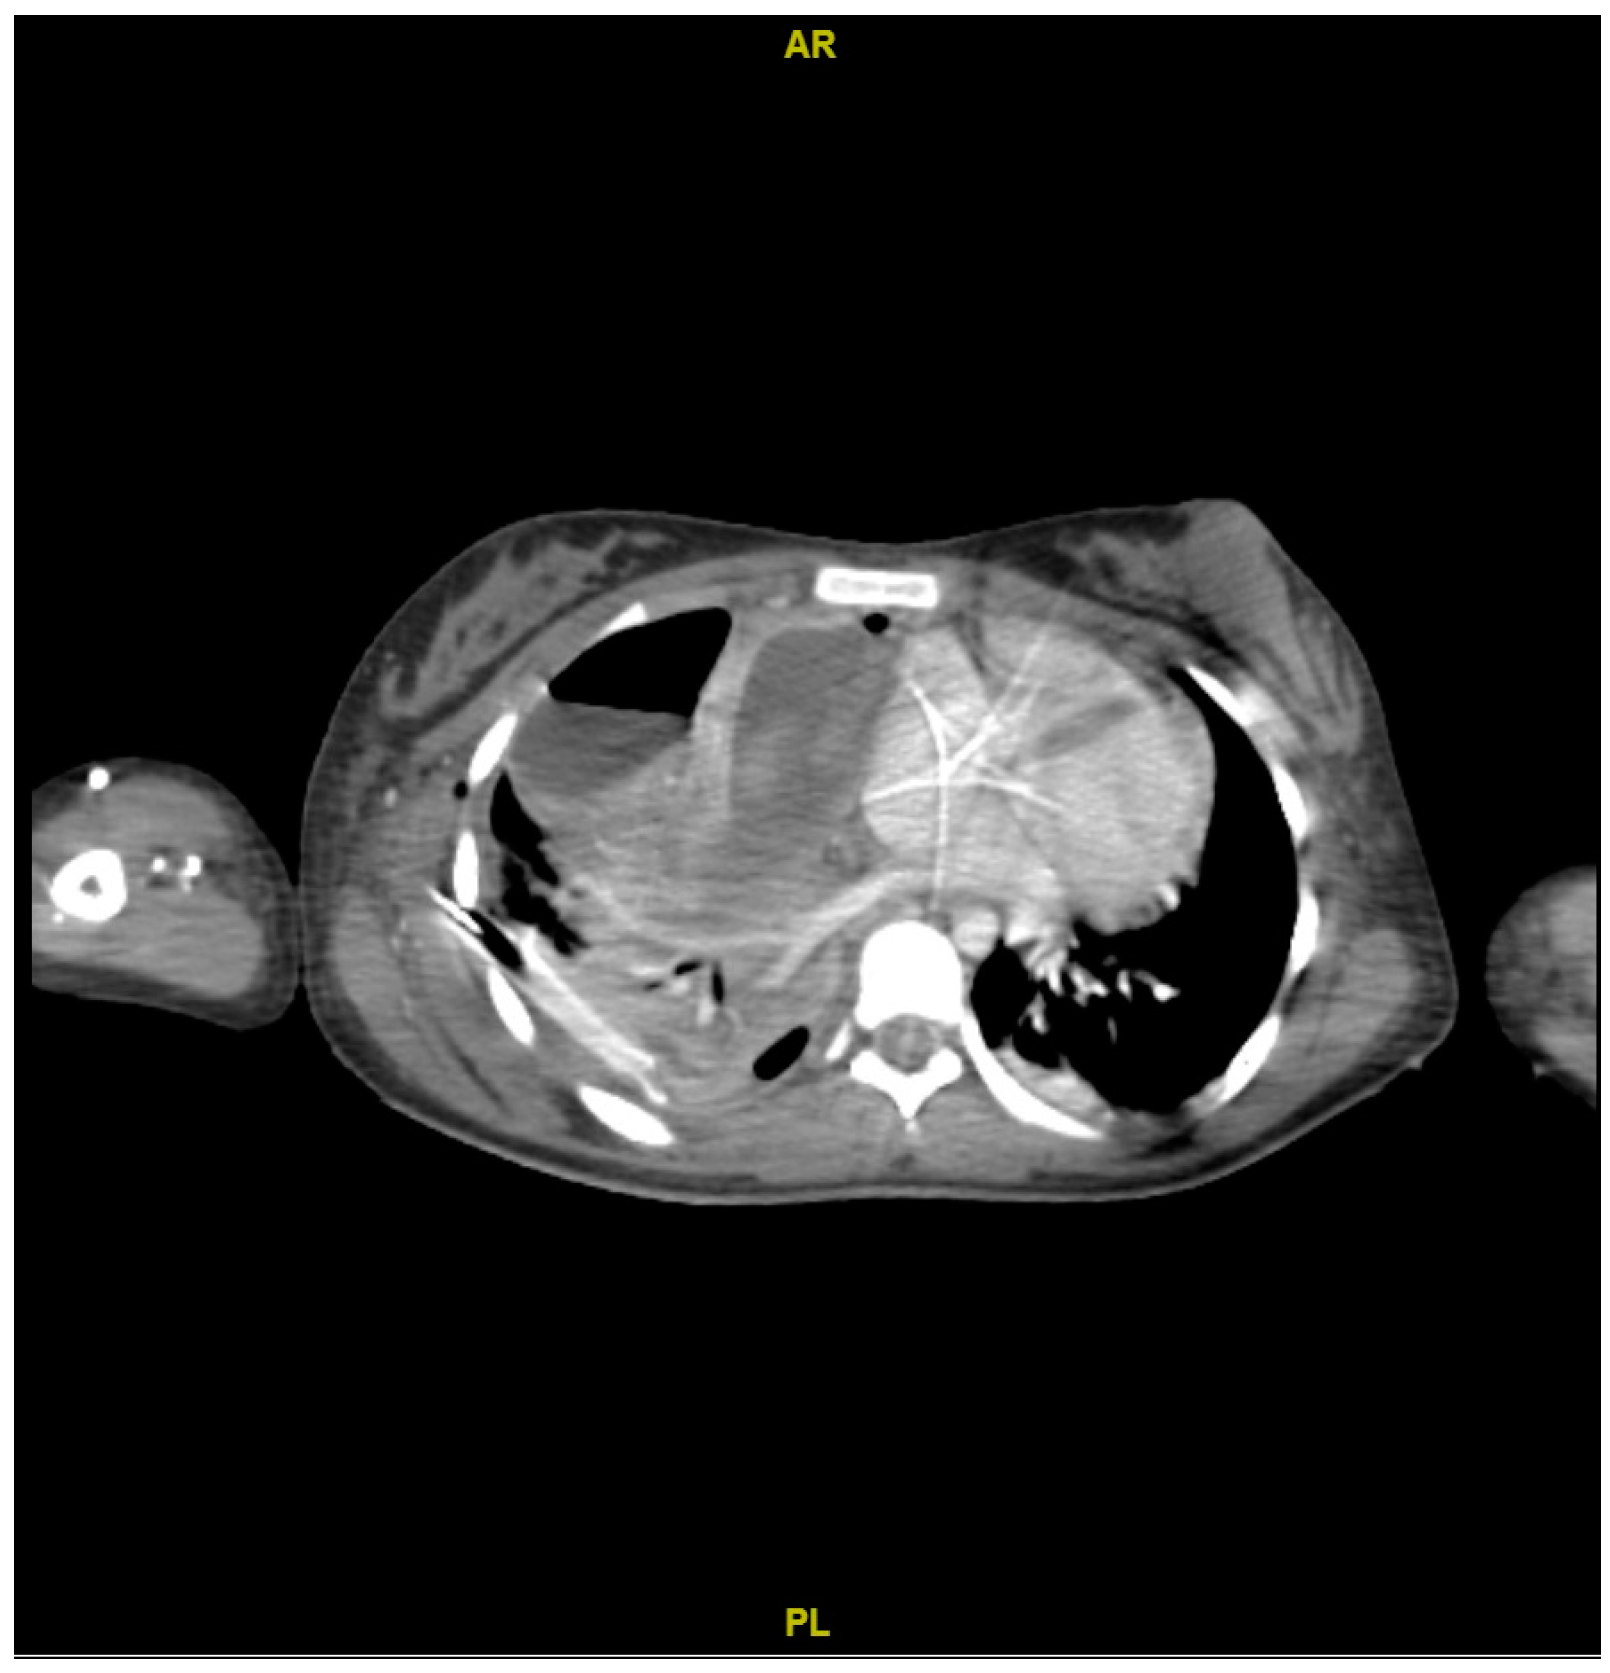

2. Case Presentation